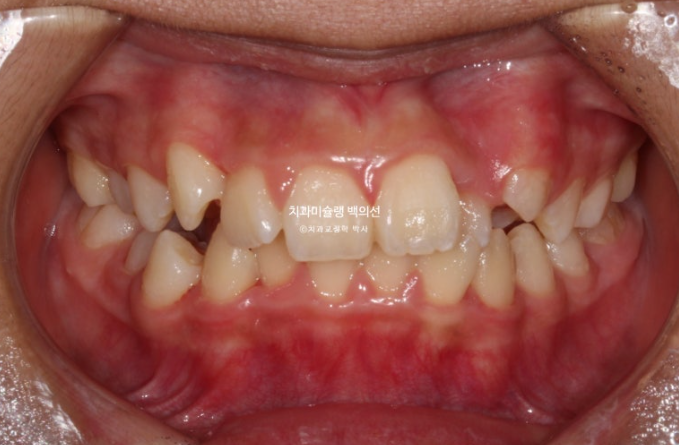

24년 1월 교정치료를 위해 온 만 10세 어린이 입니다.

24.02

3년 전에 소아치과에서 앞니 부분교정을 한 적이 있다고 합니다.

그래서 위 앞니에는 중절치 두 개를 잇는 철사유지장치가 붙어있었습니다.

중심선이 약 2mm 어긋나 있으며 위 앞니 치축은 한쪽으로 기울어져 있습니다.

앞니가 깊게 물리는 과개교합도 보입니다.

공간부족으로 인한 덧니가 심해 반대교합이 있습니다.